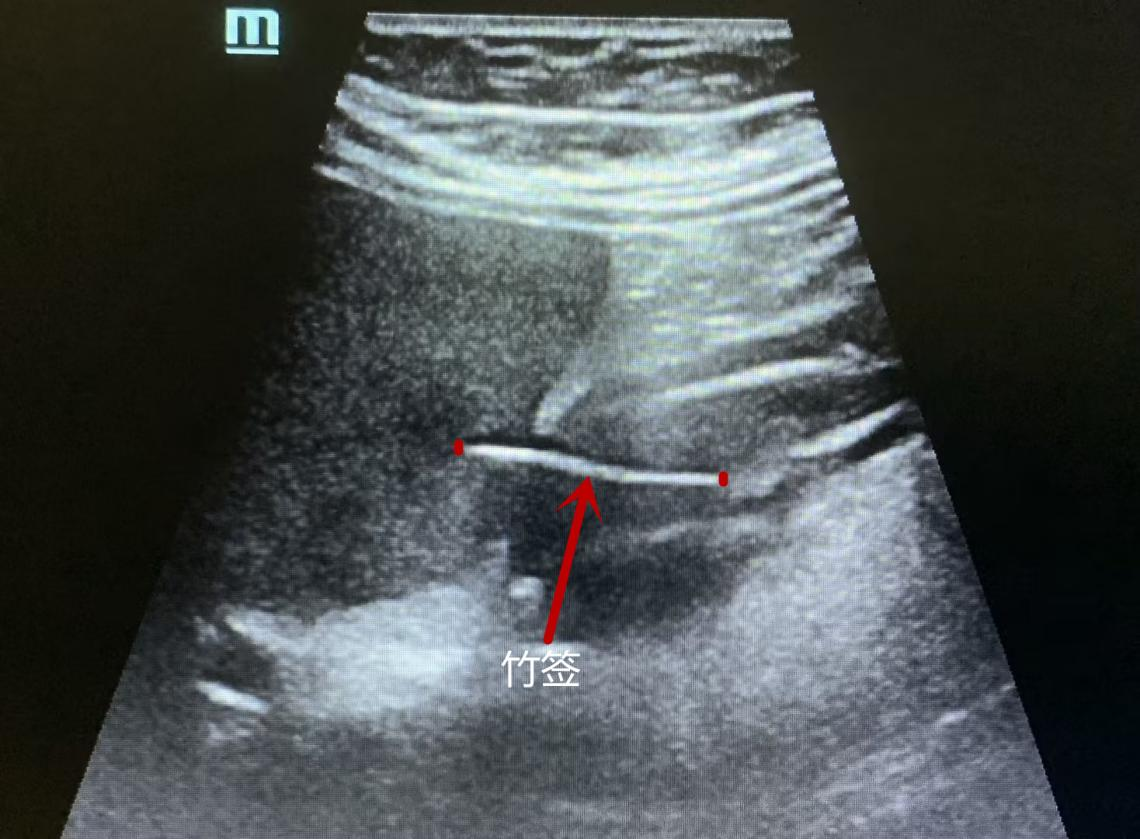

超声科谭庆亭医师反复检测,在患者的胃窦处发现了一个细细长长的异物,经张华斌主任当场会诊后,明确了诊断。此时,患者才努力地回想起,自己发病的前一天曾用竹签吃过包子。超声检查发现这根竹签已经刺破了胃壁,扎入了肝脏。“胃镜没发现是因为这根竹签的位置很特殊,它穿出了黏膜层,位于黏膜下。”超声科主任张华斌解释说。